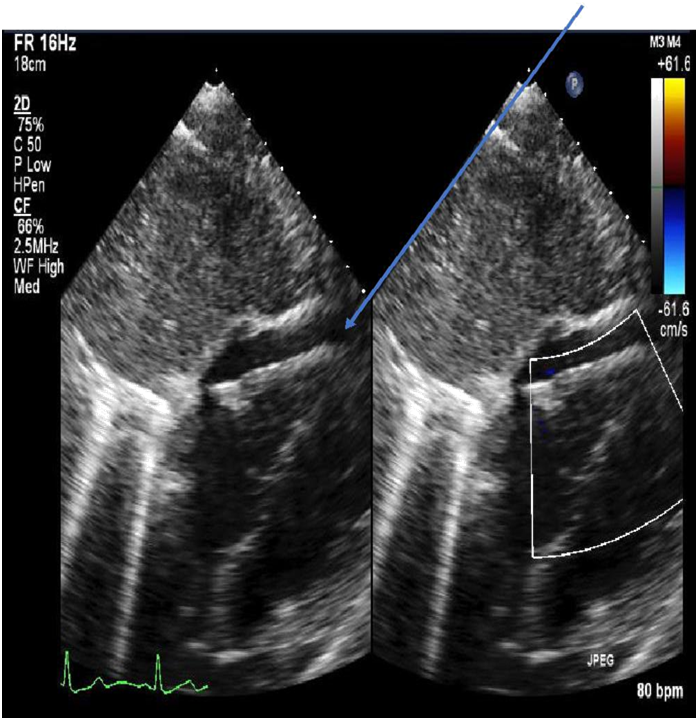

ECG revealed sinus tachycardia and right axis deviation without ST-T changes (Figure 1.). Laboratory studies, summarized in Table 1, revealed a mild normocytic, normochromic anemia and a considerably elevated serum troponin I level. Chest radiography (Figure 2) revealed a non-specific mild left perihilar/lingular area of atelectasis or infiltrate. Given her history of fever, the patient underwent technetium labeled white blood cell (WBC) scanning, prior to the onset of her chest pain, which revealed intense labeled WBC uptake at the left ventricular myocardium consistent with myopericarditis (Figure 3). A transthoracic echocardiogram (Figure 4) revealed normal right and left ventricular (left ventricular ejection fraction of 55-60 %) and a small pericardial effusion.

Figure 4 Transthoracic echocardiography (arrow indicating small pericardial effusion).

With regard to radionuclide scanning, gallium-67, indium-111, and technetium-99m have been used. Approximately 90 % of gallium-67 is retained in plasma after intravenous injection and almost all of it is bound to transferrin.12 Gallium-67 also binds to lactoferrin which has high levels in infectious foci.14,15 In myopericarditis, gallium-67 single photon emission commuted tomography (SPECT) scan usually reveals significant uptake in the myocardium and pericardium; however, use of gallium-67 over time has diminished because of its lack of specificity.14 WBC scanning to diagnose myopericarditis involves using the patient’s white blood cells, usually neutrophils, radiolabeled with technetium-99m or indium-111 antimyosin antibody and injected intravenously back into the patient, followed by single photon emission commuted tomography.15 As with the gallium scan, the WBC scan will usually reveal significant activity in the myocardium and pericardium on SPECT in patients myopericarditis.16 Both techniques of WBC scanning have been extensively used, specifically the indium-111 antimyosin antibody WBC scan. The sensitivity and negative predictive value of the indium-111 antimyosin antibody in diagnosing myocarditis were 91-100 % and 93-100 % in one study.17 The use of indium-111 antimyosin antibody scan has decreased over time because of radiation exposure and the requisite 48-hour delay in obtaining the imaging results.16 Our patient underwent a technetium-99m labeled WBC scan which revealed intense abnormal uptake in the left ventricular myocardium, with a noted small pericardial effusion.